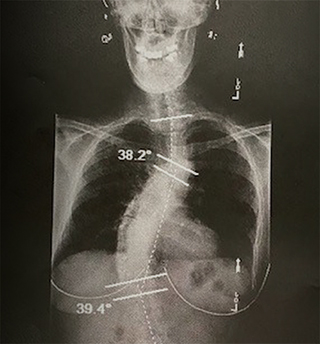

My children recommended I go see a chiropractor. When I saw the x-rays he took, I thought I was looking at someone else’s images. When I was 18, my thoracic curve was 24 degrees. There were now three measurable curves in my spine. I burst into tears at the sight of my poor body, realizing all at once why I had been in so much pain for so long.

Before the surgery, Karen’s scoliosis was compressing the nerves in her lower back, says Dr. Sardar. The procedure helped restore the normal shape of her spine and make more room for these nerves.

X-ray of Karen’s spine before corrective surgery.